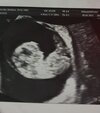

Ale piękny widok!!!Moj dziec ma juz 2.5cm i chyba o 2 dni przegonił datę transferu![]()

Adus cudownie,ciesze sie z takiego widoku,moj bubus mial 2 cm tydzien temu.Na kiedy masz termin porodu?Moj dziec ma juz 2.5cm i chyba o 2 dni przegonił datę transferu![]()

Nie wiem bo nie liczyl ale wg wielkości ciąży na 9 września a wg transferu na 11 września wiec wiadomo ze CC ma koniec sierpnia bo innego porodu nie przyjmuje do wiadomościAdus cudownie,ciesze sie z takiego widoku,moj bubus mial 2 cm tydzien temu.Na kiedy masz termin porodu?